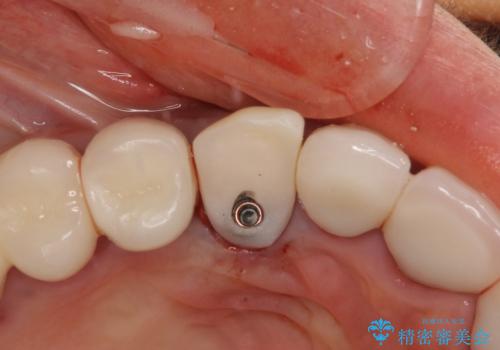

全顎的な治療後に、急遽ニューヨークへ転居されることとなったのですが、治療後から経過観察を行っていた右上犬歯が歯肉縁下に及ぶむし歯のため、クラウンが土台ごと外れてしまったとの連絡がありました。

他の部位にインプラント治療を行っていたことから、こちらの歯に対してもインプラントによる補綴治療を希望されたため、1泊での帰国時に抜歯、インプラント埋入、仮歯の装着を行い、数ヶ月後の帰国時にオールセラミッククラウンの型取りと装着を行う計画としました。

インプラント埋入時は1泊、補綴治療時には3週間ほど日本に滞在していただき、2回の渡航で無事に治療を終えることができました。